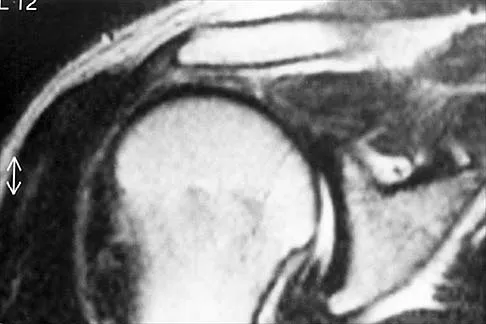

A 7-year-old patient has had a painless limp for several months. Examination reveals pain and spasm with internal rotation, and abduction is limited to 10 degrees on the involved side. Management consists of 1 week of bed rest and traction, followed by an arthrogram. A maximum abduction/internal rotation view is shown in Figure 40a, and abduction and adduction views are shown in Figures 40b and 40c. The studies are most consistent with

Explanation